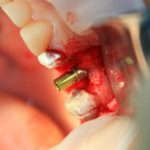

В данном случае я использовал Geistlich Mucograft Seal 8mm. Биоматериал в данном форм-факторе стоит дешевле, чем барьерная мембрана, а его диаметр позволяет легко перекрыть образовавшийся дефект слизистой:

Перед позиционированием Mucograft лучше намочить. Он станет более эластичным (без потери прочности) и мягким:

После чего, он легко приклеивается и перекрывает дефект: